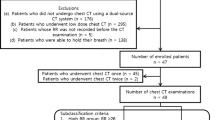

Human study

To verify whether the findings of the animal study could be translated to humans, we retrospectively analyzed chest CT scans of critically ill patients admitted at the emergency department or at the ICU. The CT scanner was a LightSpeed 16 (GE Medical Systems, Milwaukee, US), tube current was 120 kVp, pitch factor 1.75 and collimation 16 × 0.625 mm. We included only scans of patients aged ≥18 performed with a standard protocol: no contrast medium, 1-mm slice interleave, 1.25 mm thickness and medium-soft convolution kernel. From spiral scans, subsets of images including the entire lung were extracted at increasing distance between slices, mimicking the feed in sequential scans, from 2 to 50 mm in 1-mm steps.

We collected CT scans from 32 critically ill patients, whose characteristics are reported in the Additional file 1: Supplemental digital content—eTable 1. Most patients (N = 30) were included in another unrelated study concerning the assessment of lung hyperinflation in critically ill patients [23], and the analyses included in this manuscript have not been published before. For each patient, 49 subsets of images at increasing distance between slices were extrapolated and compared with the whole spiral scan, for a total of 1568 comparisons. Bias and LOA worsened at increasing slice interleave (see Additional file 1: Supplemental digital content). The accuracy of extrapolation at 20 mm of distance between slices is shown in Table 3: the number of analyzed slices decreased from 250 (233–278) to 13 (12–14) (p < 0.001). The lung cranio-caudal diameter was 250 (234–276) mm, the number of slices analyzed in the subset with interleave of 20 mm was 12 (12–14), while the current-time product was 229 (201–303) mAs. These three findings were similar to those observed in animal scans, and to the values reported in a study describing the limits of normality of quantitative CT [8].